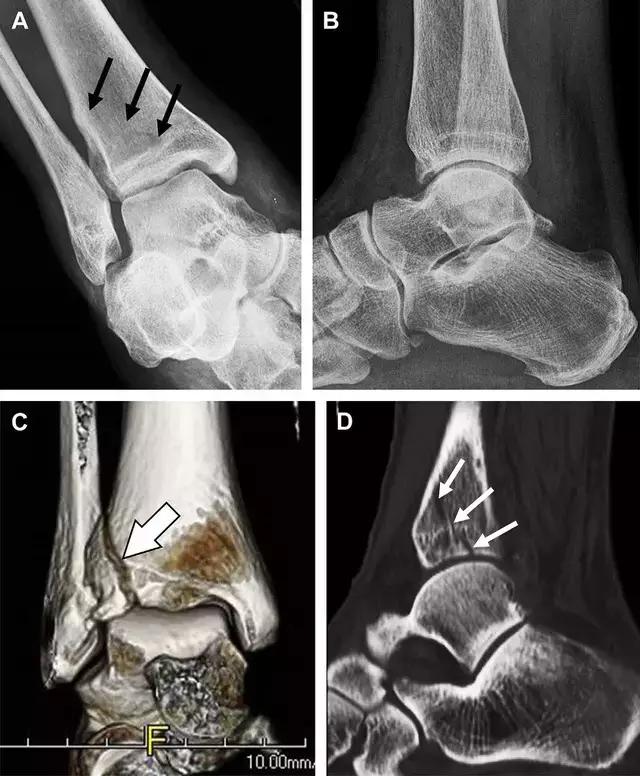

非典型股骨骨折

另一种易漏诊的骨折是非典型股骨骨折,这种骨折与长期服用双膦酸盐相关,常发生在使用双膦酸盐 3 年以上的患者。前驱症状表现为腹股沟痛或大腿痛的患者中,60%~70% 被错误地认为由腰背痛或髋关节炎引起。

这种骨折的一个典型表现为火山口状骨膜隆起及一横行透亮带。值得注意的是,超过 50% 的患者表现为股骨干完全骨折。由于 50%~60% 的患者会累及双侧,所以一旦一侧下肢确诊,需行对侧下肢检查。

图 10 老年患者长期服用双磷酸盐引起的骨折。A 髋部正位片,箭头所示,股骨外侧皮质存在横行透亮带。B 后续的股骨 X 线片示局灶性骨膜反应,以及此类骨折的特征性表现-火山口状骨膜隆起(箭头)。C MRI 冠状位 STIR 序列扫描示相应骨折平面的骨髓水肿表现